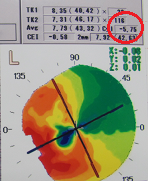

?正常な網膜です。中心部の赤い部分の網膜には、物を見るための視細胞が沢山集まっています。その周りの青にも、視細胞がありますが、赤に比べると数が少なくなります。緑はさらに見え方が落ちる部位です。

?黄斑円孔で、赤の部分の網膜が硝子体に引っ張られて断裂し、無くなってしまうと、視野の中心部が欠損、見たい部分が見えなくなってしまいます。

?手術の効果で、青や緑の網膜を中心部に引き寄せます。

?青の部分の網膜が、視野の中心部の視界を担うようになります。

赤に比べて、青の網膜は、視細胞の数も能力も乏しくなります。この青の網膜が中心部の見え方を担当するようになるので、どんなに回復しても「視力が悪い」、「感度が悪い」、「少し暗く見える」などが残り、完全に元通りという事はあり得ないのです。

青に比べて、緑はさらに感度が悪いのですが、黄斑円孔の穴が大きく、青の部分まで無くなってしまった症例では、緑が中心部の役割を担うために、さらに後遺症が大きく残ります。

⇒手術前の穴が、大きければ大きいほど術後の回復が悪く、穴が小さければ小さいほど良好な回復が得られます